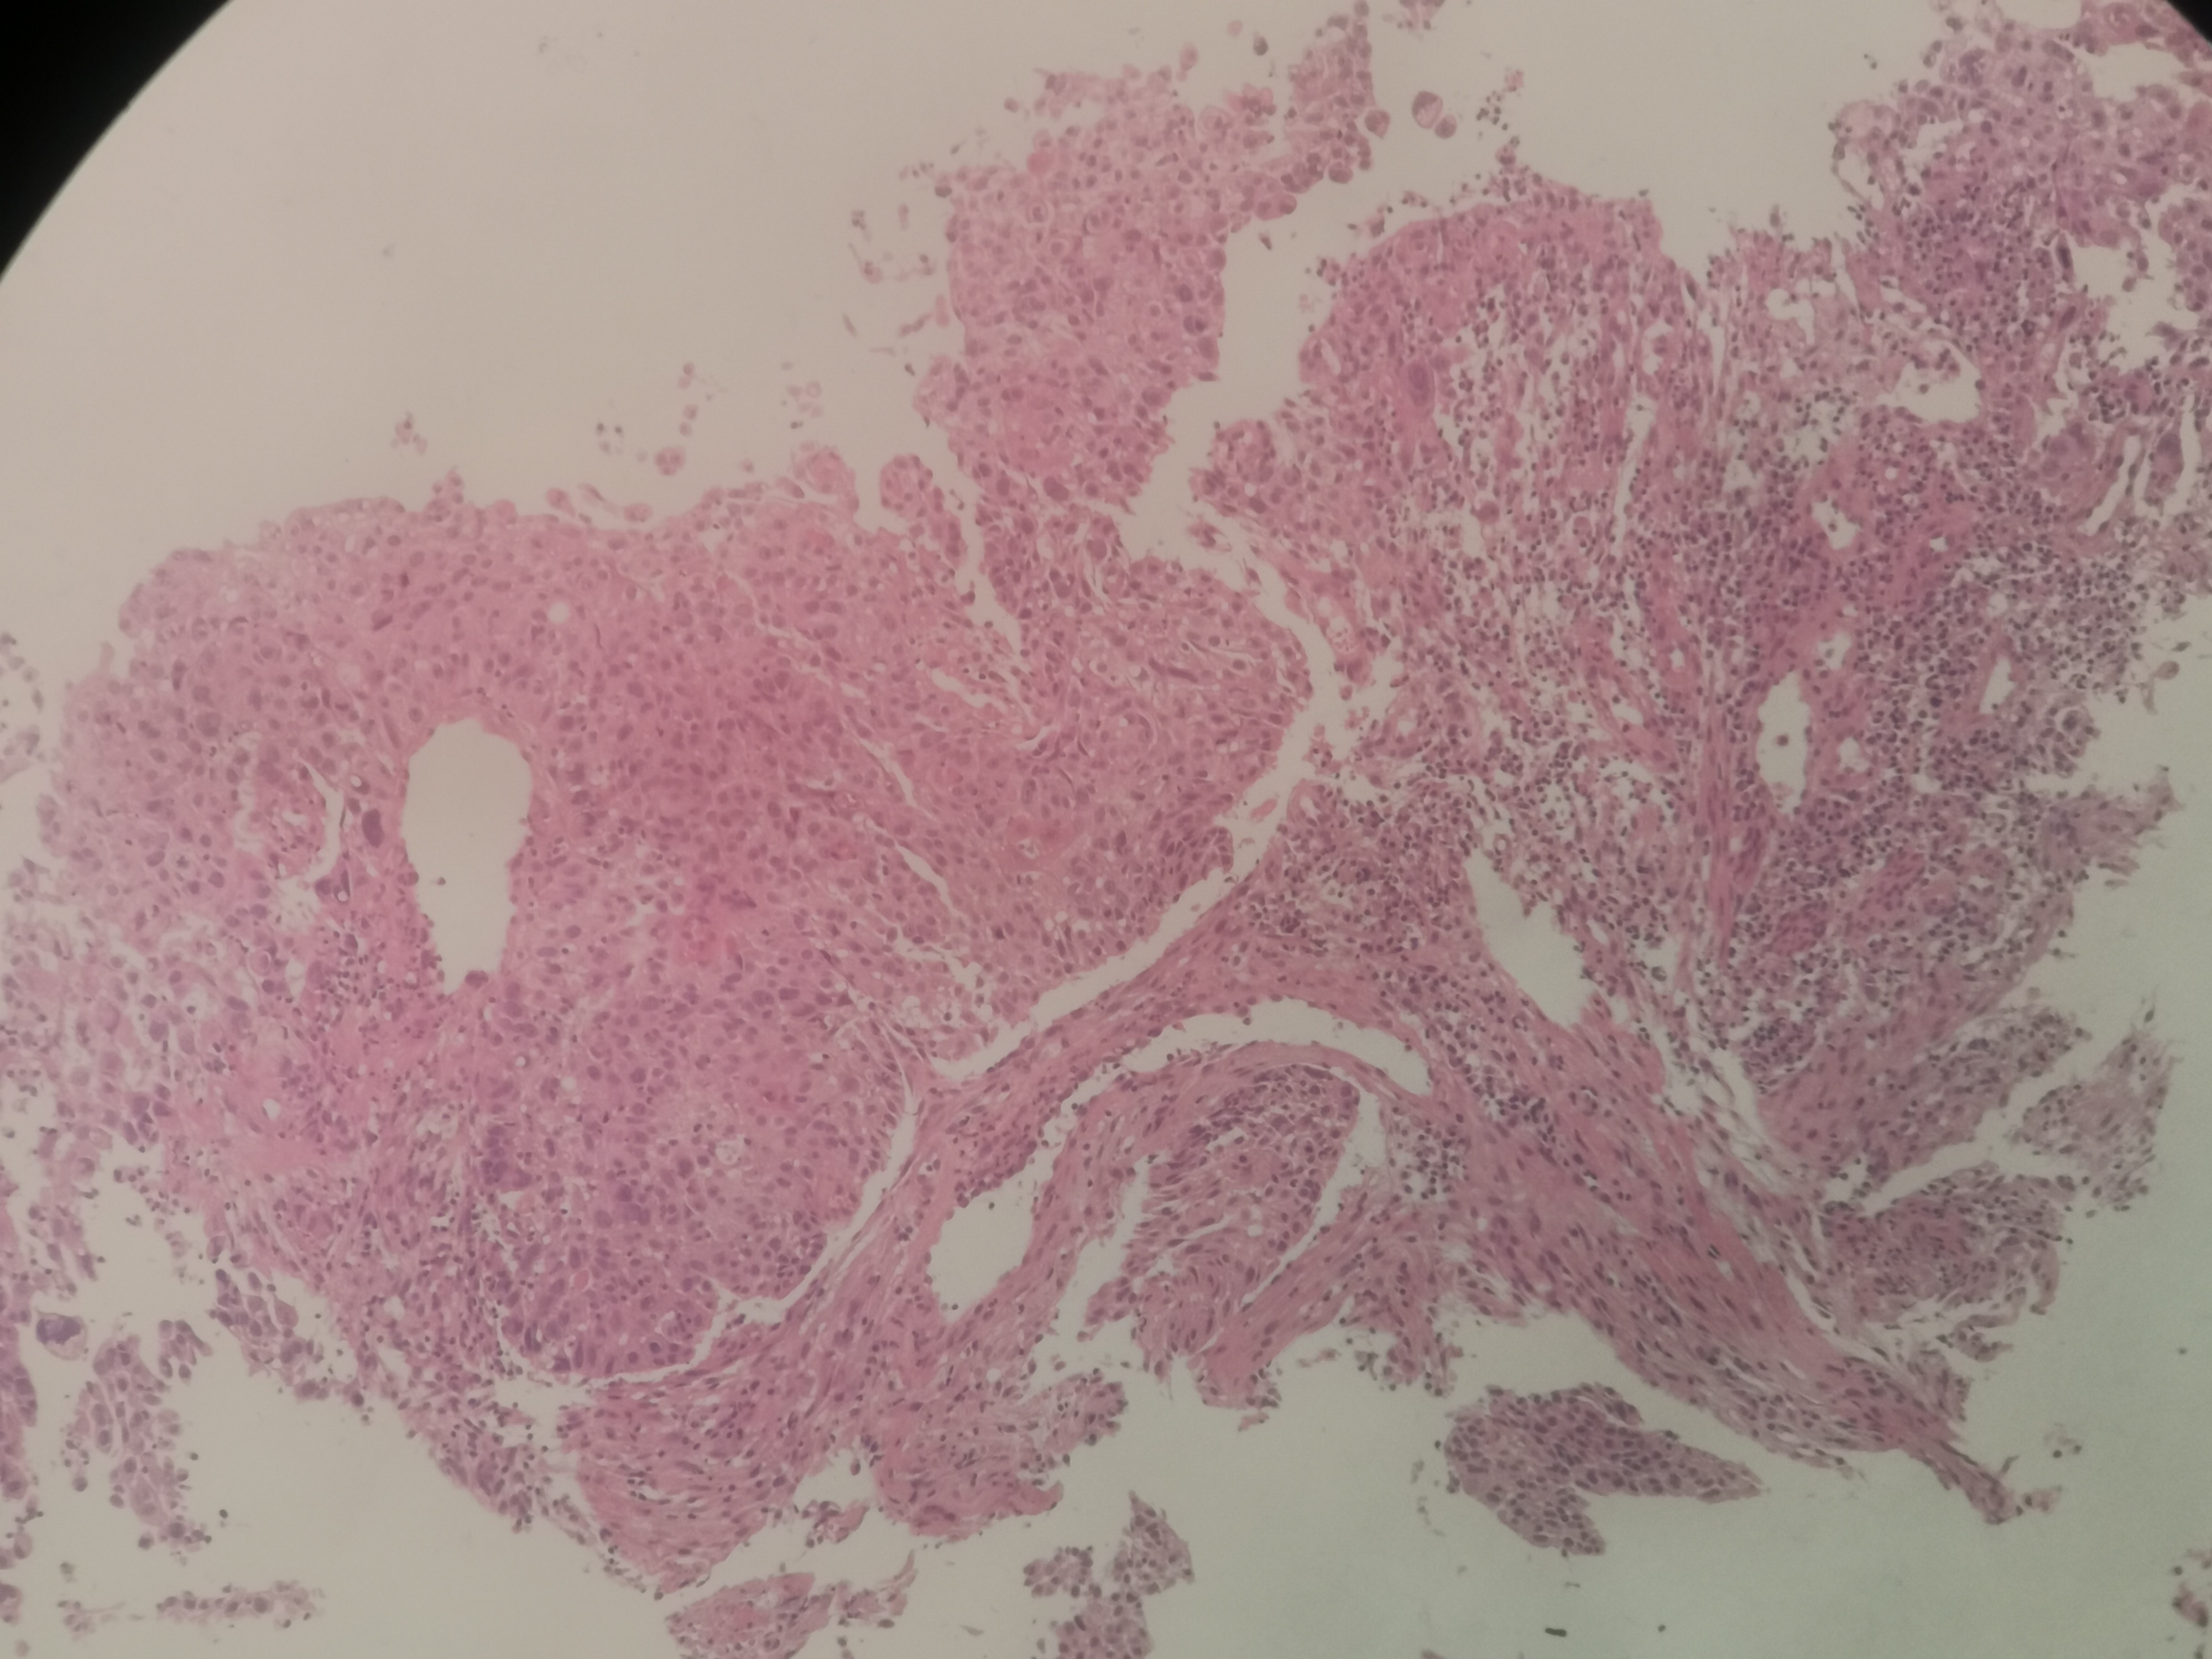

求助,请老师鳞状细胞癌高分化吗?

性别

男

年龄

55岁

临床诊断

食道肿物?

一般病史

食道35~40厘米处不规则增生性肿物,环管腔1/2表面充血、糜烂,质脆,易出血

标本名称

食道活检

大体所见

送检组织0.15x0.1x0.1厘米~0.45x0.3x0.3厘米5块

高分化鳞状细胞癌